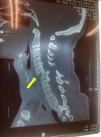

Caso 3Mujer caucásica de 50 años, sin antecedentes de interés. Tras accidente de tráfico fue ingresada sin lesiones aparentes con una TC de cráneo y columna normales. A las 24h presentó de forma progresiva paraplejía y paresia distal de extremidades superiores. Se realizó una RM urgente que mostró herniación traumática del disco C6-7, desplazamiento anterior del cuerpo de C6 y contusión medular asociada (fig. 3). Su capacidad ventilatoria se mantenía aparentemente conservada, aunque su saturación basal era del 89%. La paciente entendió y consintió nuestro plan anestésico, por lo que se realizó la misma técnica que en los casos anteriores, aunque en este caso se requirieron mayores dosis de anestesia tópica por intolerancia inicial a la cánula oral. Tampoco en este caso hubo cambios en la exploración neurológica postextubación. Se realizó discectomía del nivel afectado y estabilización quirúrgica de C5 a C7. La paciente presentó una mínima mejoría neurológica y fue trasladada a un centro especializado de lesionados medulares.